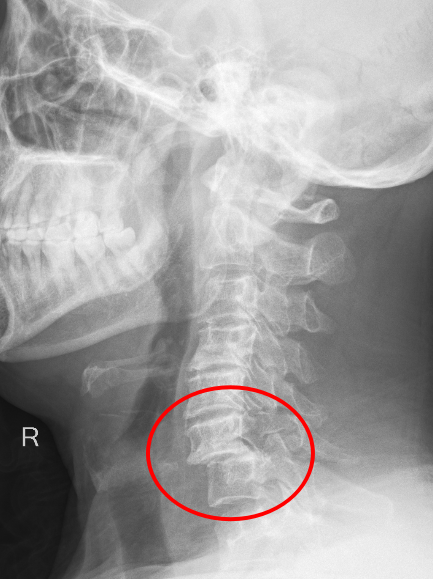

患者朱先生因意外從高處墜落,頸部劇痛、四肢麻木無力,急診入院后經CT及MRI檢查確診為第6頸椎骨折脫位伴脊髓損,隨時可能引發呼吸衰竭或永久性癱瘓。傳統保守治療風險極高,骨科主任彭李華主任醫師及脊柱專業組長張利強,迅速組織多學科會診,結合國際最新指南與患者個體情況,果斷制定“前路頸椎間盤切除+植骨融合內固定術”方案,以微創技術最大限度減少神經損傷,脊髓受壓明顯減輕,重建頸椎穩定性。

術后影像顯示,頸椎序列完美復位,內固定位置精準,患者次日即感雙上肢麻木緩解,肌力較術前明顯改善,術后第二天,患者頸部及雙上肢疼痛癥狀消失,在頸托保護能自主下床行走,術后一周痊愈出院。